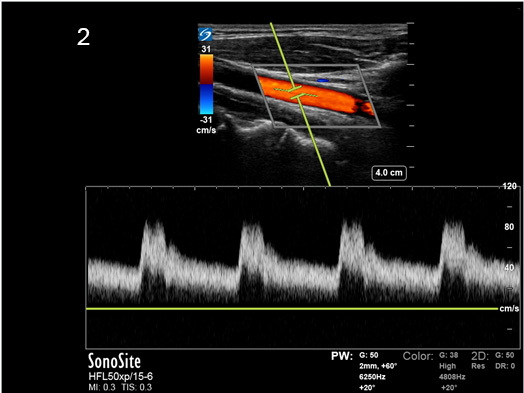

Instrumentation Sweep Speed Medium Image